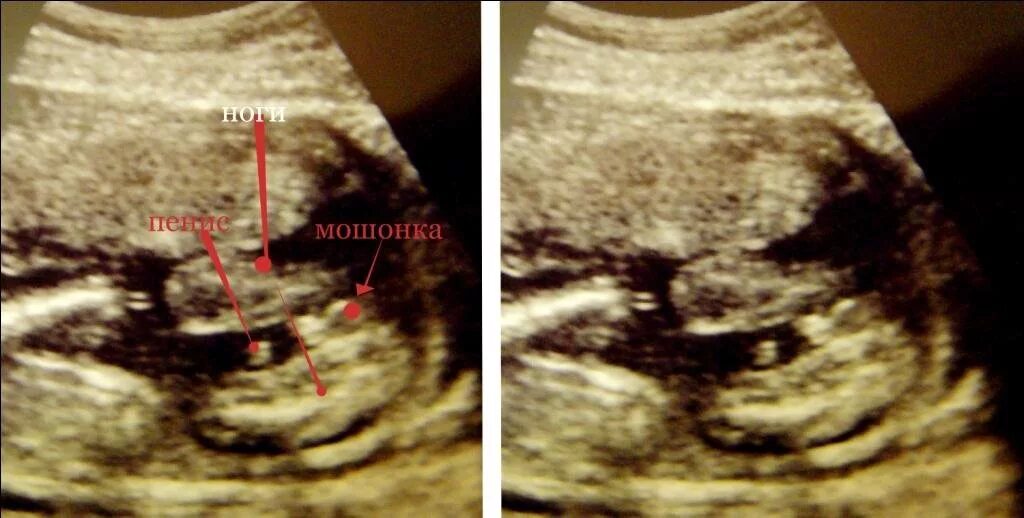

Может врач ошибиться с полом ребенка